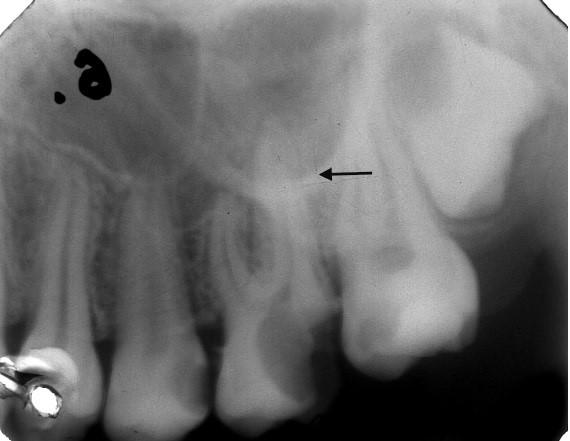

Widoczne na zdjęciu zaciemnienie radiologiczne oznaczone strzałką odpowiada obrazowi: